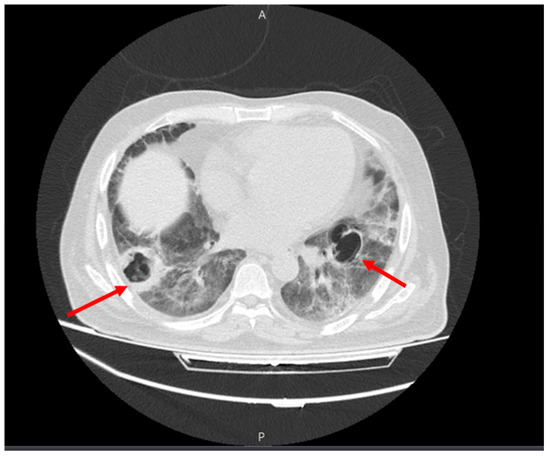

Seven days after discharge, the patient developed progressive dyspnea and frequent coughs with excessive sputum, prompting referral to the Valiasr Hospital in Zanjan, Iran. Upon admission, his SpO2 was 75%, the BP was 90/60 mmHg, the PR was 120/min, the RR was 24/min, and the T was 36.8 C degrees. A pulmonary examination revealed bi-basal fine crackles, and a lung CT was ordered, revealing cystic changes at the apex of the left lung with typical GGO changes in all lobes, consistent with COVID-19 infection. Multiple cavities with thick, septoid walls were observed in the lower lobes on both sides, with a suspected fungus ball inside one of the cavities on the left side. No plural effusion or lymphadenopathy were seen upon imaging (Figure 3).

Figure 3.

Multiple cavities with thick, septoid walls in the lower lobes on both sides (red arrows).